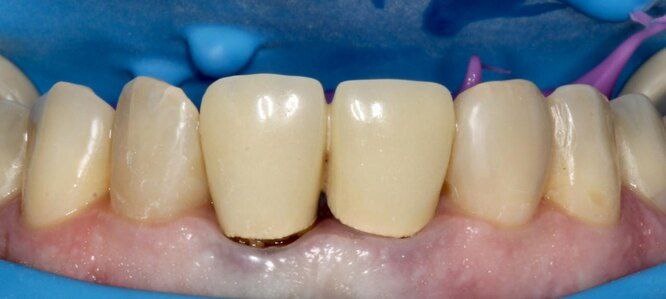

Одна из самых распространённых причин — оголение края коронки со временем. На стыке зуба и коронки образуется поднутрение, где скапливается налёт.

Если вовремя не заметить проблему, начинается воспаление и разрушение пришеечной части зуба.